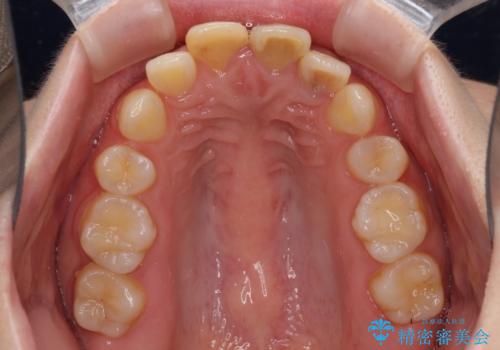

抜歯矯正の後戻り インビザラインによるオープンバイトの再矯正

- 以前矯正治療をされていましたが、後戻りが起きたことを気にして来院された患者様です。

上下前歯のオープンバイトを改善するため、インビザラインにて治療を行うこととしました。

外食が楽しみである患者様だったので、インビザラインによる治療期間は我慢の時期であったようです。

自己管理を徹底していただいたので、1年程度で治療を終えることができました。